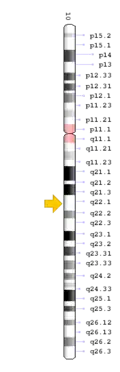

TNFRSF11A mutation

The TNFRSF11A gene is present in chromosome locus 18q21.33, which encodes for the receptor activator of NF-κB (RANK).[13] RANK is expressed in immature osteoclasts, which facilitates osteoclasts maturation upon binding of RANK ligand (RANKL). Binding of RANK ligand mediates the RANK/RANKL/OPG signalling pathway. The pathway mediates osteoclast differentiation and activation by promoting differentiation of precursors into multinucleated osteoclasts, and activating osteoclasts, thereby contributing to bone resorption and remodelling. Health conditions related to genetic changes in TNFRSF11A includes osteopetrosis, osteolysis, and Paget's disease of bone.[14][15]

Multiple reports of gene mutations exists underlining the mutation of the exons and introns leading to aberrant splicing. There are five variants to the TNFRSF11A gene which produces five unique protein iso-forms. The effects of alternative splicing on each variants are unclear. However, it is suggested that such changes lead to different expression patterns of the gene in both space and time. Some mutant splicing variants would undergo nonsense-mediated mRNA decay (NMD), while others would not be subjected to NMD, and instead produce a truncated isoform of the RANK protein. The mutated protein has structural defects hence hinders normal function in the signalling pathway, contributing to development of the disease.[14][15]